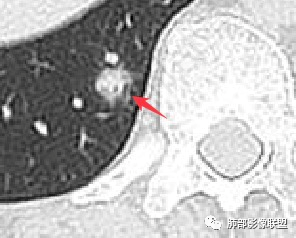

请大家仔细观察这个条索,与胸膜相连,局部结节感。这个大概率是小叶间小静脉的走行。

![]()

这里有个特点,是偏侧的,不是reid's小叶 的一圈“隔”都增厚,是局限性的。这种增厚,什么原因可以引起呢?比如:血管的问题,里面有肿瘤。比如淋巴道的问题,有癌淋,或者有间质纤维的不规则增生。

请仔细观察病灶周围情况,比如临近血管、临近胸膜。有个特点,胸膜牵拉并不明显,邻近血管走行还算正常。

这里,可以佐证了。假如支气管扩张是收缩力引起的,而且支气管扩张如此明显,它周围的组织不会一丁点表现没有,离胸膜如此的近,竟然一点牵拉的意思都没有。